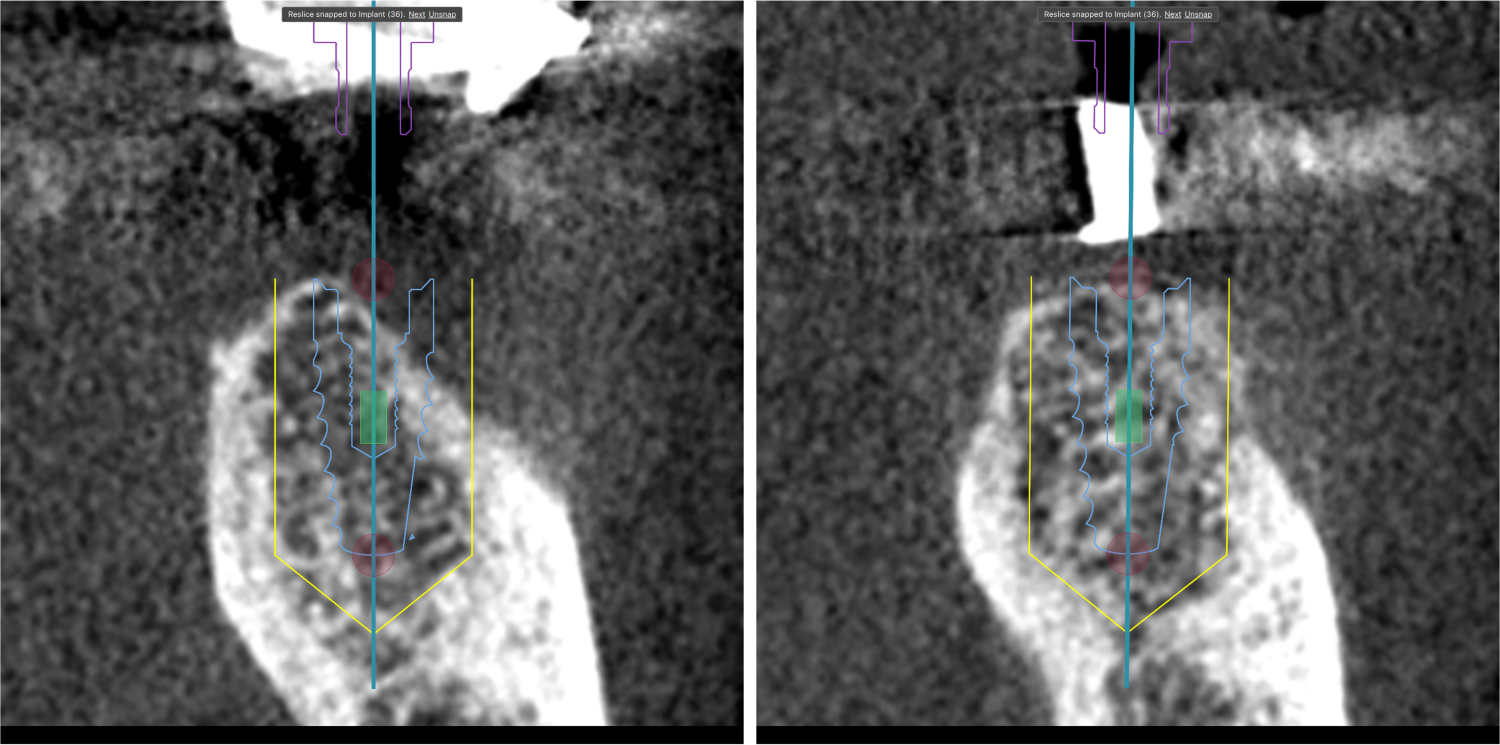

上顎、下顎の欠損のインプラント治療の症例(うえだ歯科)

| 治療内容 | プラークコントロール不良なため歯周治療を行い、残存歯を極力温存し、欠損部インプラントを施し咬合再構成を行う。 プロビジョナルレストレーションによる咬合関係を模索した後、全顎にわたりセラミックによる補綴治療、その後メインテナンスに移行 |